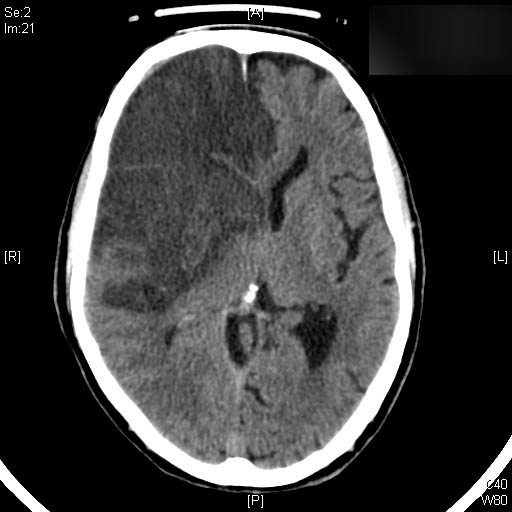

Hematoma subdural por caída.